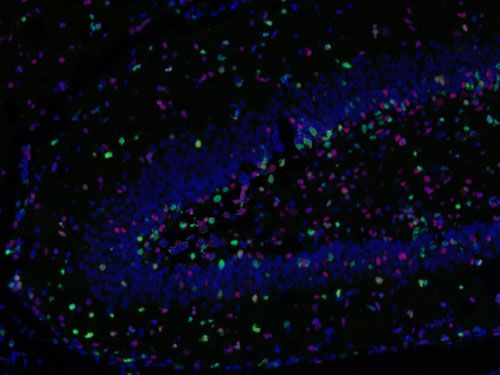

□免疫熒光多標陽性共定位分析:

測量整張掃描切片或者指定區域中單獨通道的數據以及指定共定位的數據(陽性面積或陽性率值表示,選其一)。

免疫熒光空間距離分析:

主要用來研究腫瘤微環境,炎性細胞和腫瘤細胞之間的距離關系等。

□分析一種指標標記的細胞周圍多少微米范圍之內另一指標標記的細胞數量,可以設置不同范圍;

□分析不同指標標記細胞之間的平均距離;

□以某處為界(如腫瘤灶、壞死灶或指定區域等)分析該區域多少微米范圍之內不同指標標記的細胞數量,例如腫瘤周圍500um內CD3陽性細胞的數量。